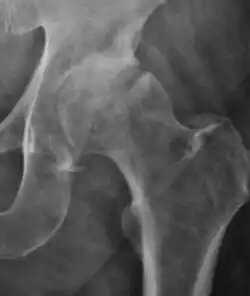

Plain radiography allows us to categorize the hip as normal or dysplastic or with impingement signs (pincer, cam, or a combination of both). Besides these, pathologic processes like osteoarthritis, inflammatory diseases, infection, or tumors can also be identified (Figure 1).[1]

Figure 1.

-

Radiography in normal hip -

X-ray in pincer impingement type of hip dysplasia -

X-ray of cam -

Hip in osteoarthritis -

Septic arthritis

In adults, one of the main indications for radiographs is the detection of osteoarthritic changes (Figure 1(e)). Nevertheless, radiographs usually detect advanced osteoarthritis that can be graded according to the Tönnis classifications. The grading system ranges from 0 to 3, where 0 shows no sign of osteoarthritis. Intermediate grade 1 shows mild sclerosis of the head and acetabulum, slight joint space narrowing, and marginal osteophyte lipping. Grade 2 presents with small cysts in the femoral head or acetabulum, moderate joint space narrowing, and moderate loss of sphericity of the femoral head. Grade 3 is the severest form of osteoarthritis, which manifests as severe narrowing of the joint space, large subchondral cyst with productive bone changes that may lead to deformity of the bone components of the joint, while secondary osteoarthritis due to calcium pyrophosphate deposition can be diagnosed when calcification of hyaline cartilage and fibrocartilage is detected.[1]

There are other pathological conditions that can affect the hip joint and radiographs help to make the appropriate diagnosis. Acute bacterial septic arthritis can be diagnosed by radiographs when a fast regional osteoporosis and destructive monoarticular process develops (Figure 1(f)). In case of tuberculous or brucella arthritis it is manifested as a slow progressive process, and diagnosis may be delayed.[1]